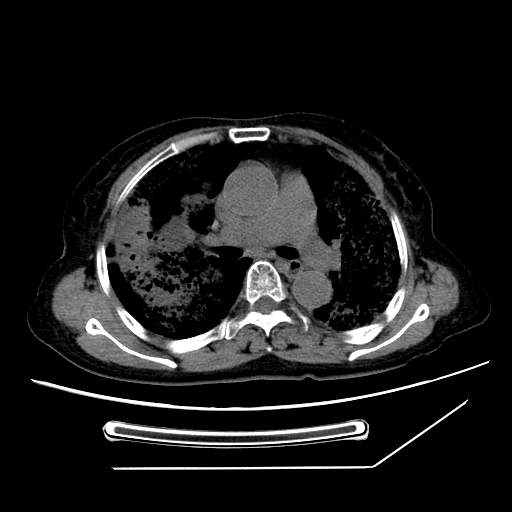

标题: CT25393:病人45岁,咳嗽,吐黄痰带血丝,发热,胸闷月余 [打印本页]

标题: CT25393:病人45岁,咳嗽,吐黄痰带血丝,发热,胸闷月余

1、左肺中央型肺癌并双肺弥漫性转移   2、双肺部感染    3、肺大泡     4、左侧胸腔积液

双侧肺弥漫性病变,可见“空泡征”及“蜂窝征”,考虑肺泡癌可能性大,左侧胸腔积液,考虑胸膜受累可能!

考虑肺泡癌,建议排除感染。

考虑肺泡癌

1)不排除肺泡癌可能。2)左侧胸腔积液。